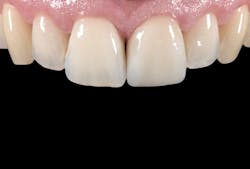

After examining the position, shade, and stability of the hard and soft tissues, we decided to treat the case with a nonprep veneer made from lithium disilicate for tooth 9. For the restoration material, we chose IPS e.max Press HT (Ivoclar) because of its impressive esthetic properties (figure 2). The veneer was produced by dental technician Roberto Della Neve in Naples, Italy.

A follow-up examination was performed 10 days after the placement. The tooth structure had rehydrated during that time, allowing me to assess whether the veneer had integrated successfully. The patient and I were both very pleased with the esthetic result. The visual impression of the anterior front is beautiful and harmonious. The dainty veneer looks completely natural and unnoticeable (figure 14).